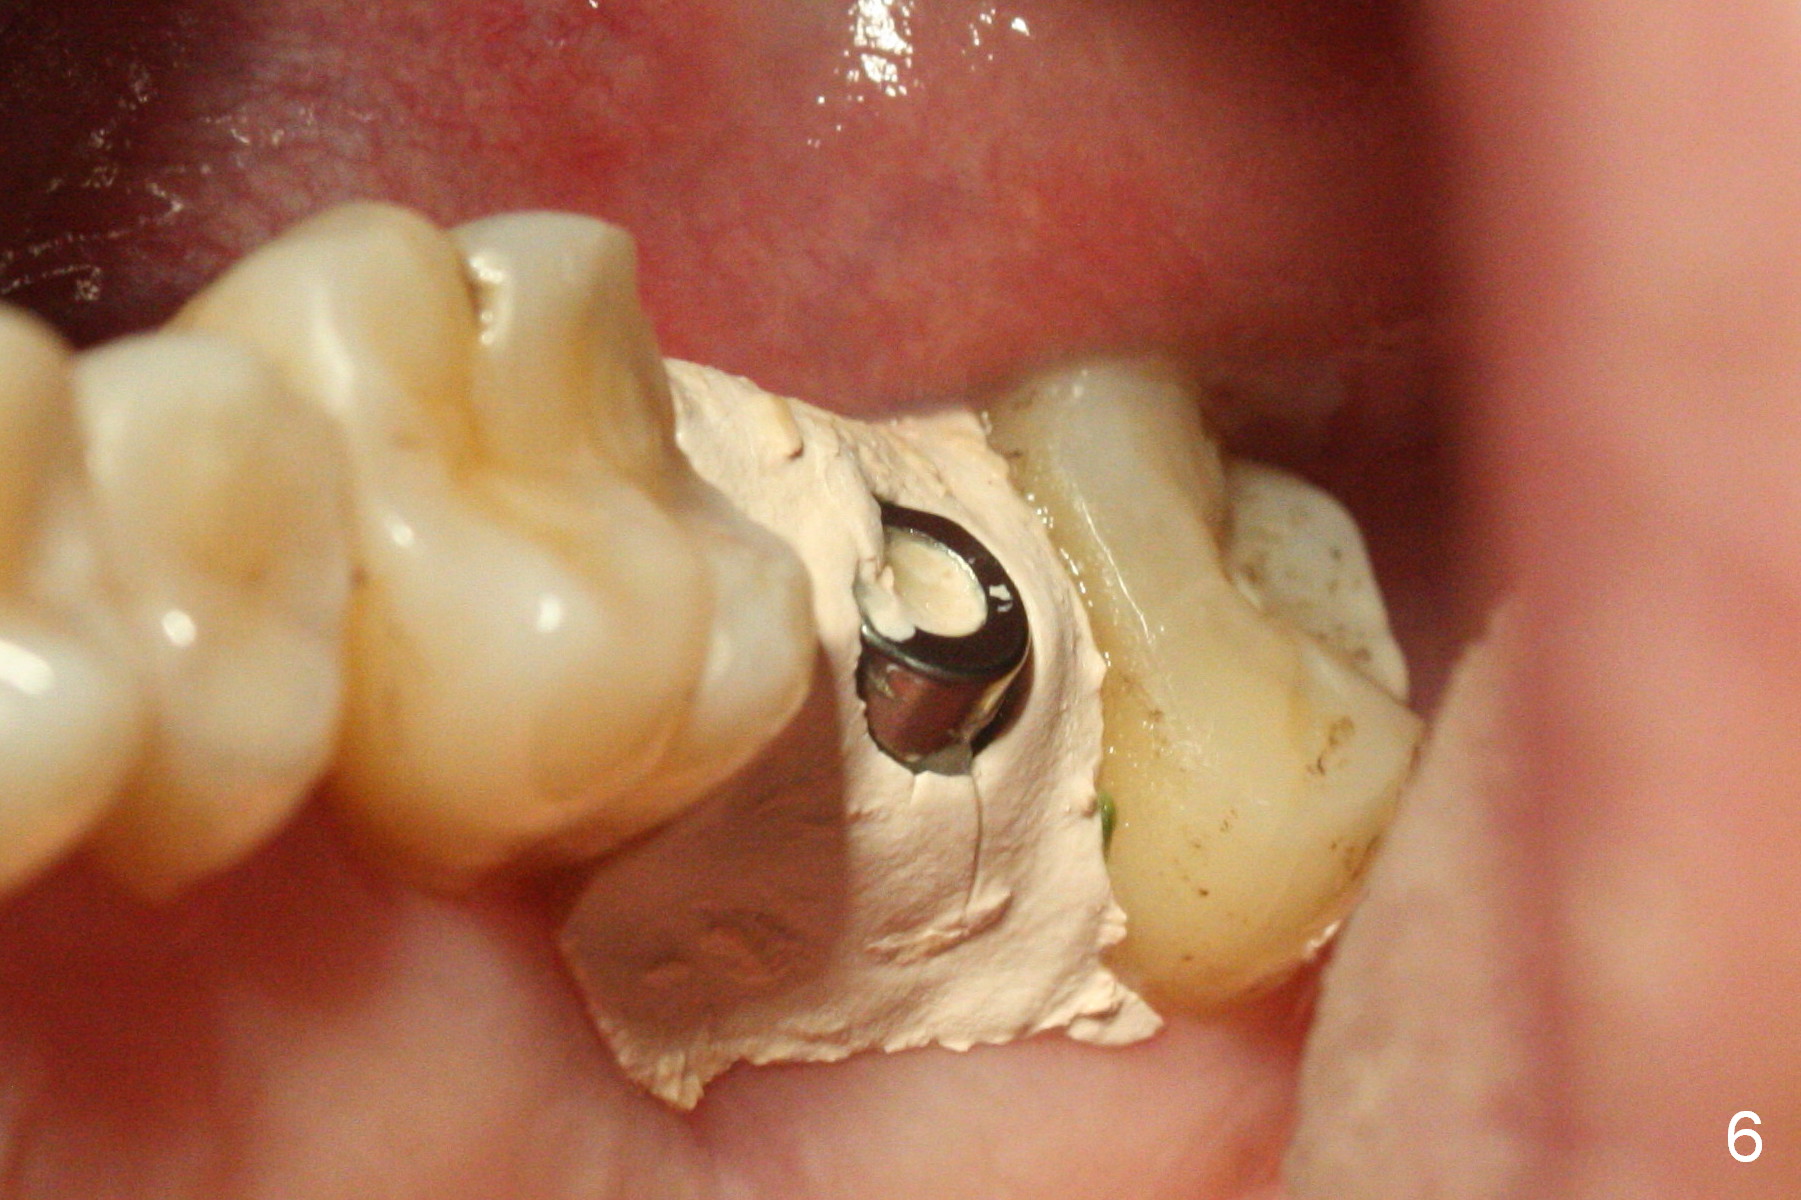

An immediate provisional is laid outside the buccal gingiva to prevent loss of bone graft, but a large gap develops underneath the provisional buccally with loss of bone graft, noted 1 month postop. The buccal gingiva is also found to perforate after removal of the provisional. These are related to the extensive preop buccal plate loss. The buccal threads are exposed. After induction of hemorrhage from the surrounding healthy granulation tissue, Osteogen plug is placed in the buccal gap, covered by periodontal dressing, which stays 9 days postop (Fig.6).